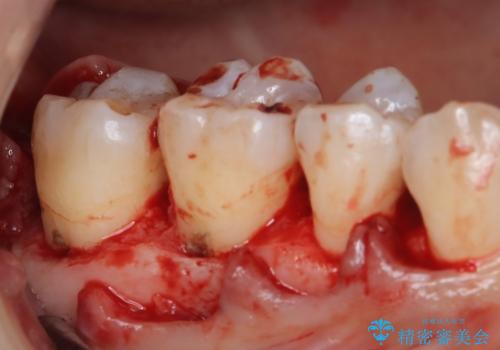

- 定期的にクリーニング(保険適応)に通って頂いている患者さんです。歯周ポケットが4ミリあったため歯茎を開いて歯石を除去するためにオープンフラップ術を行うことにしました。

歯周ポケットがそれほど深くない患者さんでしたが、いざ歯茎を開いてみるとそこにはたくさんの歯石がありました。もし歯周ポケットが4ミリだからと言って放置していれば数年後には、沢山の骨が無くなっていたことが予期出来ます。現段階で歯茎の下にある歯石を除去することにより骨が無くなることを予防する事が出来ました。